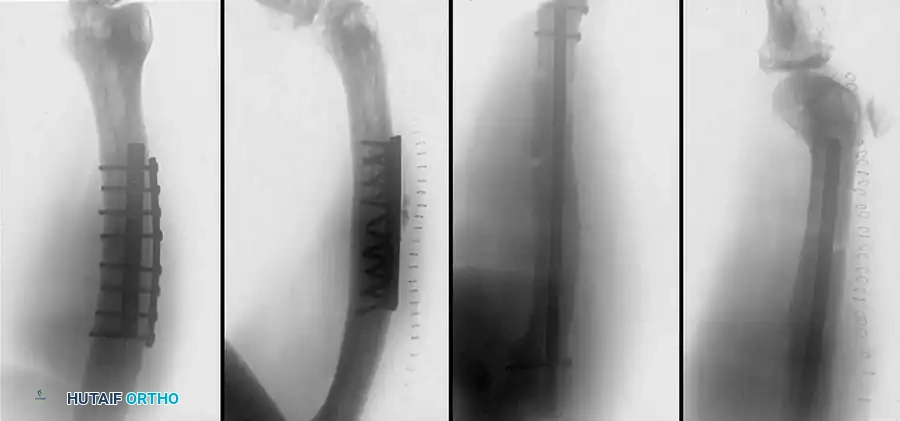

Fig. 51-91 Femoral shaft fracture stabilized with plate and interfragmentary screws.

AO Principles and Clinical Outcomes

Since the 1960s, AO surgeons have utilized compression plate fixation. The most accurate anatomical reduction of comminuted fractures can be obtained with interfragmentary lag screws and neutralization plating. However, historical open plating techniques required massive soft-tissue stripping, leading to unacceptable rates of infection and implant failure.

Modern Biological Plating (MIPO)

Modern plating techniques emphasize biology over absolute mechanical rigidity. Mast and others proposed indirect reduction of intermediate fragments, preservation of medial soft-tissue attachments, and bridge plating. Most femoral shaft fractures treated with indirect reduction heal with robust secondary callus formation rather than primary cortical healing.

Riemer et al. demonstrated excellent results using indirect reduction and posterolateral plate application without medial bone grafting in blunt polytrauma patients. In their series of 141 fractures, the average time to union was 18 weeks, with a 99% return of full knee extension.

If plate fixation is indicated, a broad Low-Contact Dynamic Compression Plate (LC-DCP) or Locking Compression Plate (LCP) should be used. The scalloped undersurface of modern plates preserves periosteal blood supply. Generally, a minimum of eight cortical screws (four bicortical screws) should be placed on either side of a transverse fracture.